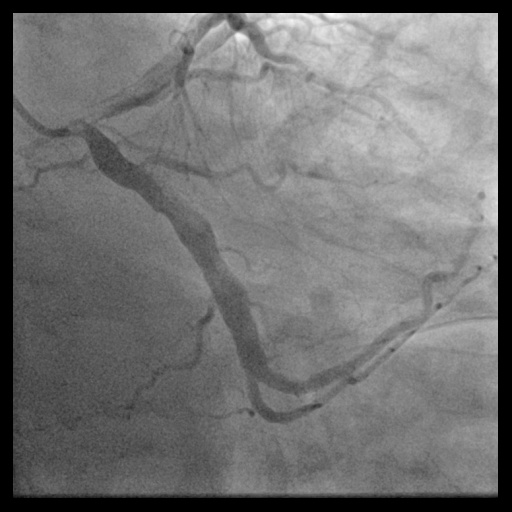

After 3 days of anticoagulation, follow-up CAG via the right radial artery with a 7 Fr in 6 Glidesheath Slender revealed a persistent thrombus along the RCA. A 7.0 Fr AL 1.0 Medtronic Launcher guiding catheter advanced an ASAHI Fielder FC 0.014” wire into the distal RCA. IVUS (Boston Scientific, USA) revealed extensive thrombus and an aneurysmal RCA segment. Regular aspiration catheters were ineffective, pushing thrombus away rather than aspirating it. A 5 Fr JR 4.0 catheter with an angulated tip enabled direct thrombus extraction. Continuous suction successfully removed a large elastic thrombus, which was extracted with the AL1 catheter. The sheath was replaced, and the guidewire reinserted. Repeated aspiration and thrombus fragmentation using a 5.0 mm x 15 mm NC Emerge balloon cleared the mid-RCA thrombus but failed for the distal thrombus. A 7.0 Fr KANEKA Thrombuster II catheter also failed to remove distal thrombus. A second vascular access via the right femoral artery with an 8 Fr Terumo Glidesheath Slender enabled use of the Penumbra ACE68 catheter (Penumbra Inc., Alameda, CA, USA), known for its large lumen and excellent trackability. The ACE68 catheter successfully aspirated the distal thrombus. To restore patency, a 5.0 mm x 12 mm Medtronic Resolute Onyx stent was deployed in the mid-RCA, followed by post-dilation with a 6.0 mm x 12 mm NC Emerge balloon at 20 atm. Final angiography confirmed TIMI grade 3 flow, achieving full reperfusion.